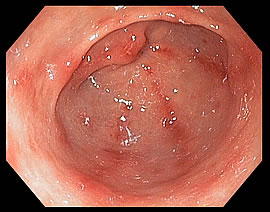

Poliposis Gástrica

Los pólipos gástricos (PG) son lesiones originadas en la mucosa gástrica que se presentan frecuentemente y de manera incidental. Aunque la presencia de pólipos en el estómago es un hecho bastante frecuente, su diagnóstico es generalmente casual, al ser en la mayoría de los casos asintomáticos. El término poliposis gástrica difusa hace referencia a la presencia de múltiples pólipos que cubren gran parte de la mucosa gástrica.

La polipectomía gástrica es una técnica que se realiza por vía oral aplicada al tracto superior digestivo que tiene como finalidad la resección de pólipos.